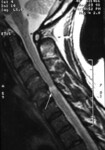

Doença degenerativa da coluna cervical

Um único nível de compressão da medula espinhal com alterações em T2, na sequência sagital cervical de T2 na presença de mielopatia cervical degenerativa sintomática